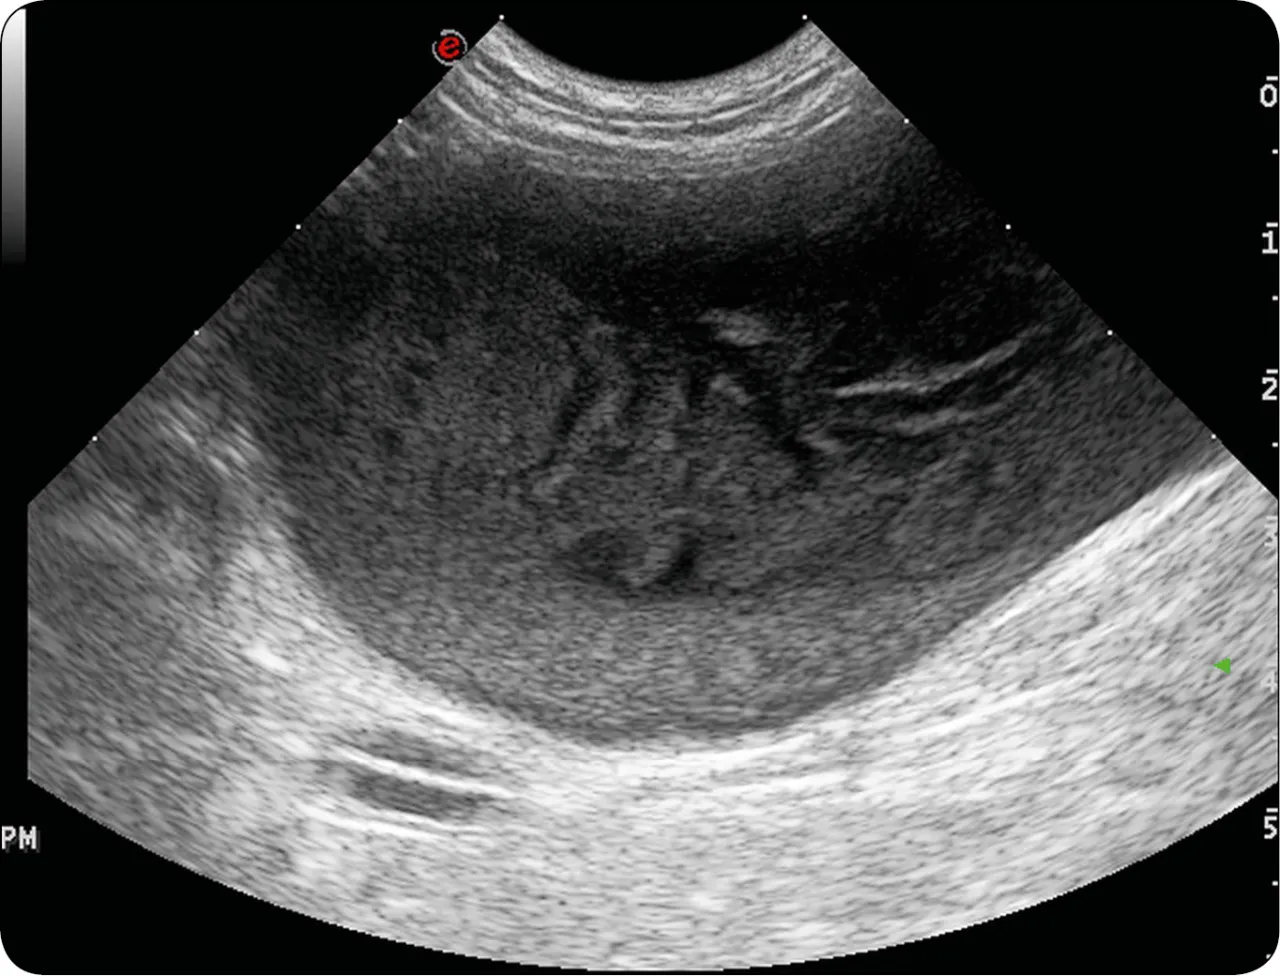

Kluczowym elementem diagnostyki jest badanie moczu, które może ujawnić obecność bakterii, krwinek białych czy czerwonych. W niektórych przypadkach konieczne może być wykonanie posiewu moczu, aby zidentyfikować konkretny szczep bakterii i dobrać odpowiedni antybiotyk. Czasami weterynarz może zalecić również badanie USG jamy brzusznej, aby wykluczyć obecność kamieni moczowych lub innych nieprawidłowości anatomicznych.

| USG jamy brzusznej | Wykrycie kamieni, anomalii anatomicznych |